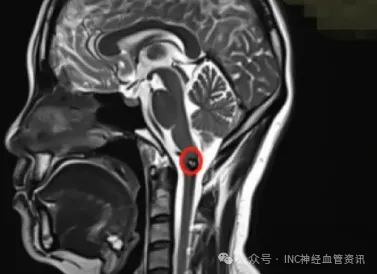

瑜伽、羽毛球、高強度工作如今的王女士,身上幾乎找不到曾經歷開顱手術的痕跡。 但時間倒回2017年,她正面臨一個艱難的抉擇:要不要為腦干深處的隱患冒險手術? 王女士30歲,延髓海綿狀...